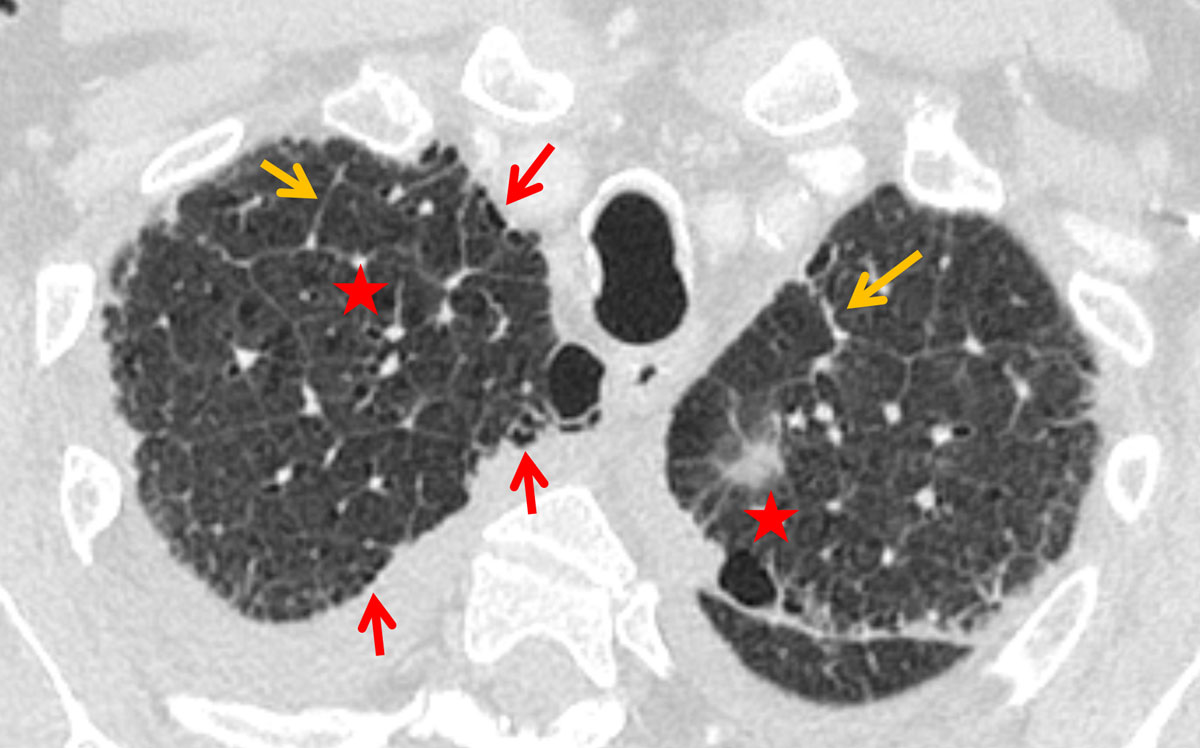

Interlobular septal thickening (IST) in the lung apex was present in of 81% and 76% of the cardiac and renal groups, respectively, which was significantly more than in the ILD group (26%, p <0.0001, figs 1–4 ). The distribution in the insufficiency group was more homogenous throughout the lungs than in the ILD group, in which the amount of septal thickening increased to 90% towards the lower lobes (table 2). The average thickness of the interlobular septa was rated between 1 and 2 with significantly thicker septal lines in the insufficiency group (1.45 ± 0.6) compared with the ILD group (1.28 ± 0.5; p <0.0001, fig. 3).

Figure 3 Interlobular septal thickening (orange arrows), slight architectural distortion (asterisks) and a faint honeycombing (red arrows) in a 70-year-old male patient with idiopathic pulmonary fibrosis (IPF).

In this study, more than 80% of the patients with cardiac insufficiency and more than 70% of the patients with renal insufficiency presented with IST (Kerley B lines) in the lung apex. Miniati et al. described an identical distribution of the septal lines on conventional chest x-ray in the lower lungs among patients with heart or renal insufficiency [19]. While their distribution in the insufficiency group was homogenously throughout the lungs, the amount of Kerley B lines in our study increased to 90% towards the lower lobes in the ILD group. Findings of ILD predominate in the lung bases [8]. Patients with heart or renal insufficiency showed peribronchial cuffing due to increased capillary hydrostatic pressure or decreased oncotic pressure [1, 20]. One reason for the apical prevalence of the Kerley B lines in congested patients could be the redistribution of the pulmonary blood flow into the cranial parts of the lung, probably increasing the capillary pressure with resultant transudation. Kerley B lines are not a new sign in chest radiology, but their location in the lung apex is here described for the first time.